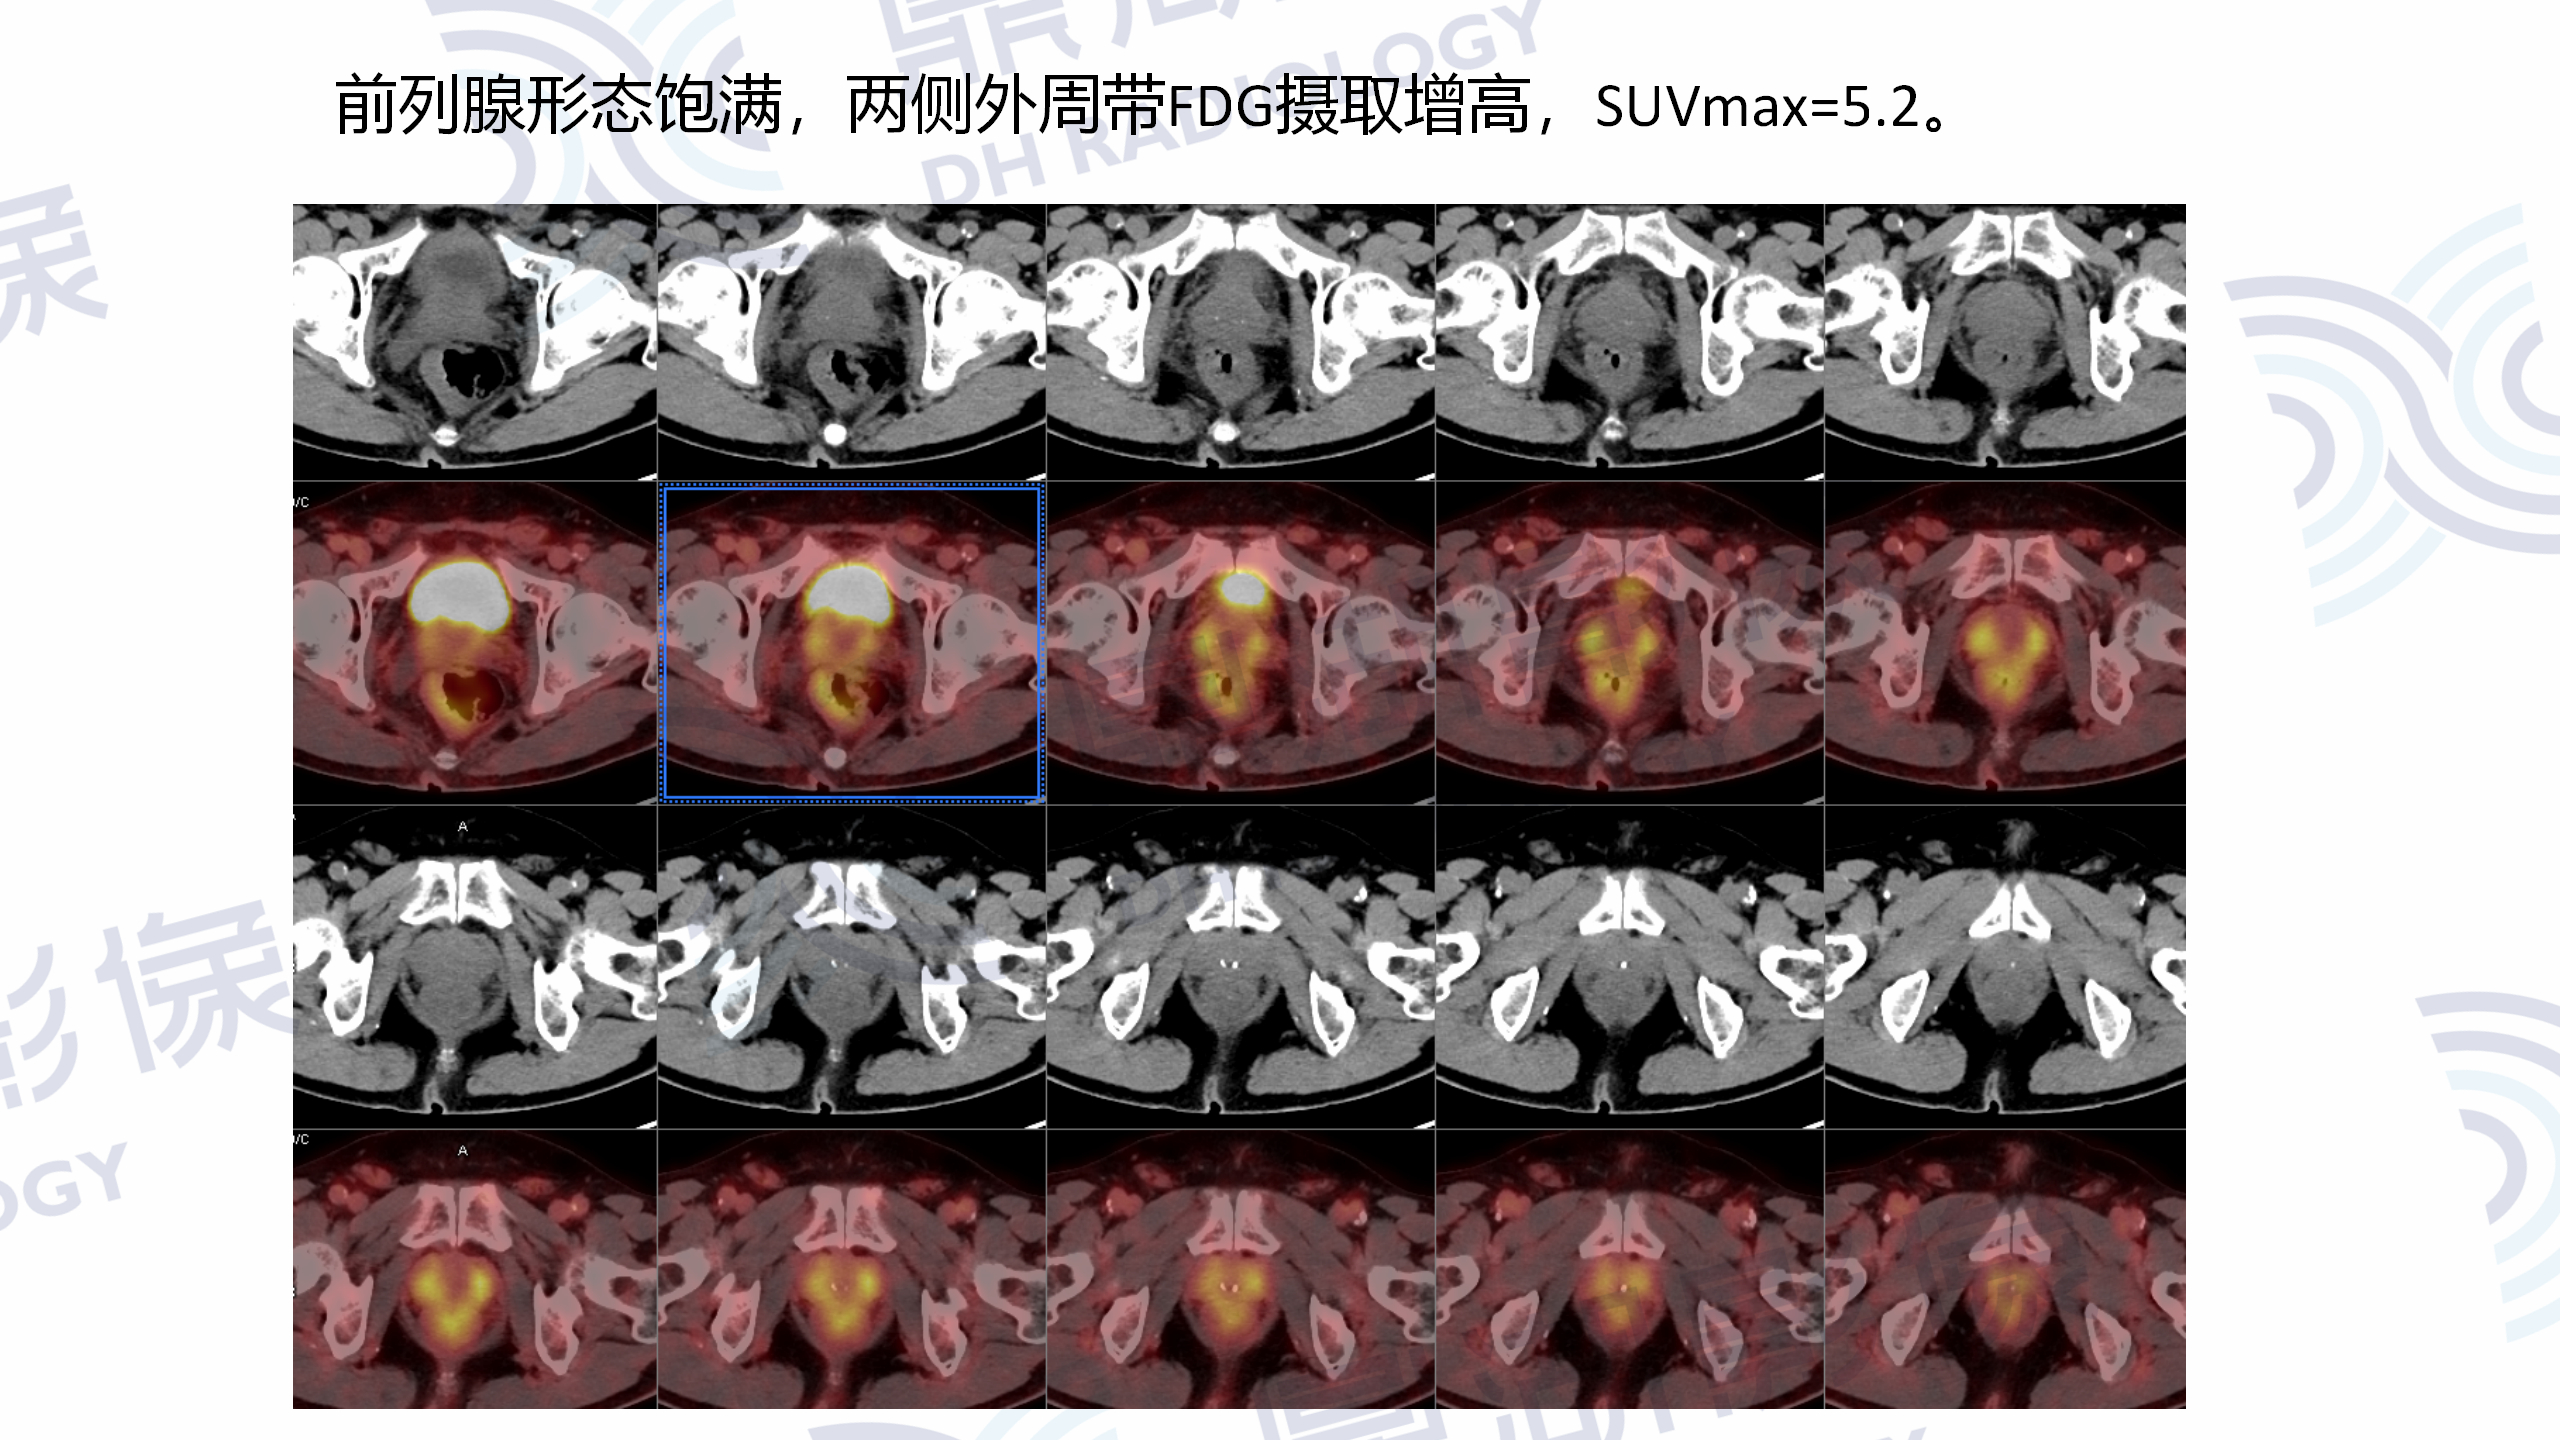

女  23岁  咽部不适1周,喉镜检查示咽部新生物,无疼痛发热等症。血常规实验室检查未见明显异常。本中心MR检查提示口咽恶性肿瘤,疑淋巴瘤可能,于本中心进一步行PET/CT检查。

MR增强检查提示:口咽左侧壁至左侧声门上不规则软组织肿块,病灶突入咽腔,信号均匀,T1WI呈等信号,T2W呈稍高信号,DWI呈高信号,增强扫描呈轻度均匀强化,左侧杓状会厌皱襞水肿,左侧梨状窝消失。

PET/CT提示:口咽左侧壁至左侧声门上软组织肿块,FDG摄取增高,SUVmax=13.1。

口咽部活检病理为淋巴组织增生,IgG4浆细胞浸润阳性。